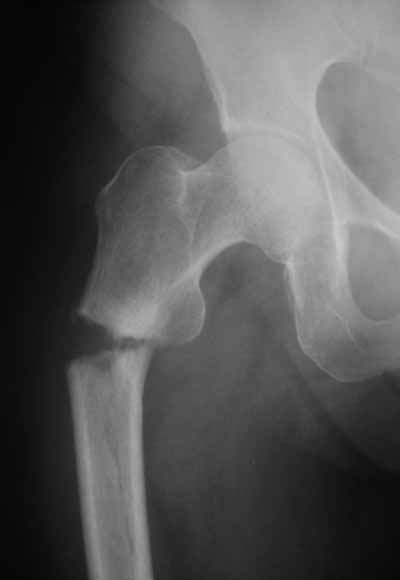

Да? Качество рентгенограмм конечно неочень, но ведь это нестабильный перелом 31.А2.2, не так ли?

Не думаю так. см вложение.